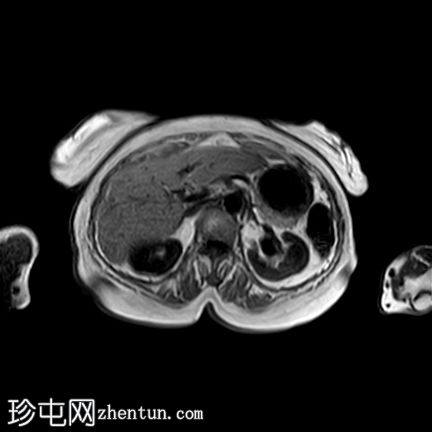

轴位

T2

2.jpg

子宫呈U形,宫底轮廓消失,宫底突出至扩张的阴道内,宫颈位于内翻的宫底上方(II级子宫内翻):

宫底处可见阴道内可见边界不清、分叶状实性肿块,明显扩张阴道壁,阴道壁完整。

肿块最大轴向及头尾径约为 9.7 x 9.6 x 9.5 cm,T1 加权像呈低信号,T2 加权像呈中/高信号,伴有扩散受限和不均匀增强。

肿块前方压迫膀胱,后方紧邻乙状结肠,未见侵犯。

肿块压迫左侧远端输尿管,导致轻度输尿管肾积水。

轴位MRI:可能显示靶环状或同心环状结构,提示子宫内膜存在不同层次。